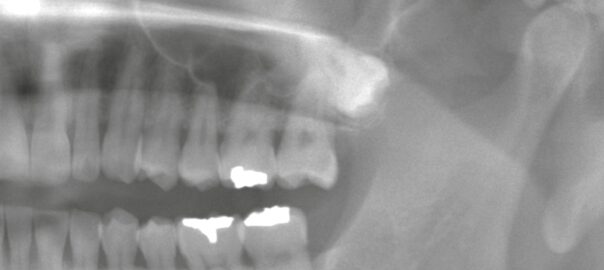

- 2025/09/10 ブリッジからインプラントへの移行 ― 右下臼歯の症例

こんにちは、静岡市駿河区石田の小嶋デンタルクリニックです。 本日は「ブリッジが破折した後にインプラントで咬合を回復したケース」をご紹介します。 ご来院の経緯 患者様は右下の奥歯に痛みを感じて来院されました。 確認すると、 … 続きを読む ブリッジからインプラントへの移行 ― 右下臼歯の症例